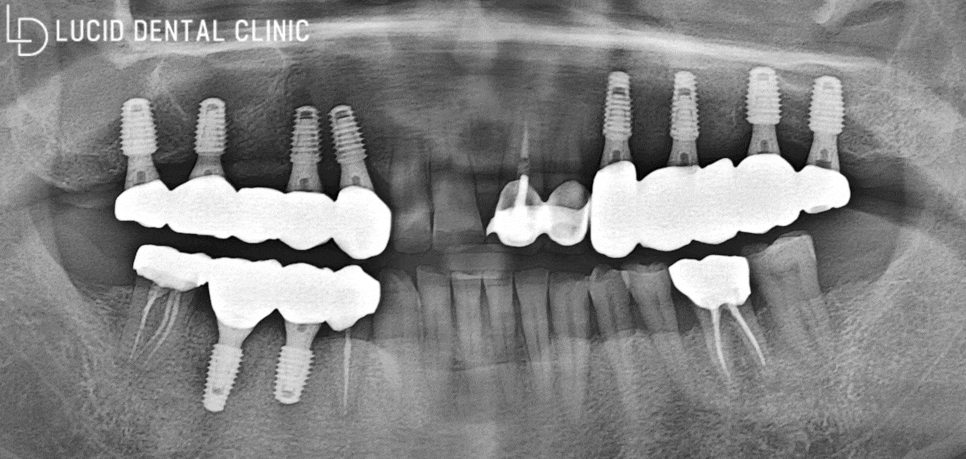

- 최종 종료

임플란트 수술 을 모두 종료하고

촬영한 파노라마 엑스레이입니다.

제대로 고정이 되지 않아 흔들거리고,

통증으로 불편했던 초진 모습관 다르게

보다 튼튼하고 안정적인 모습으로

구강에 심어져 있는 걸 볼 수 있죠?

게다가 서초동 치과 에서 제작한 크라운은

자연치와 유사한 색조와 형태로 제작하여

보다 높은 심미성을 자랑하고 있어요 ㅎㅎ